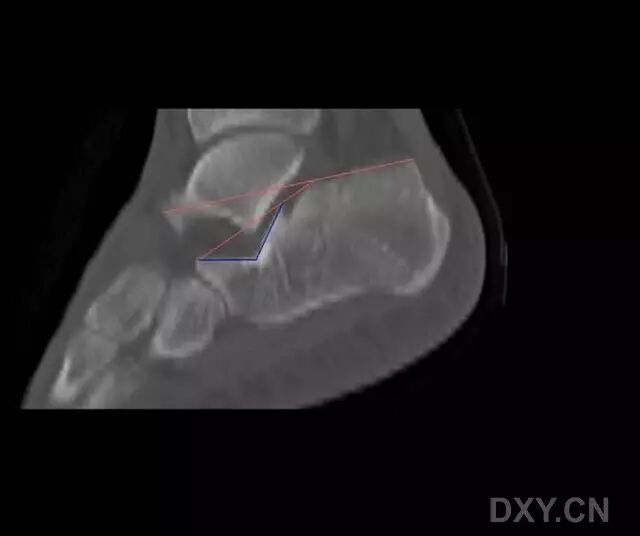

跟骨解剖非常复杂,在三维上,存在多条关节轴线(图 1)。跟骨后关节面呈凸起状,并向后内侧倾斜以支撑距骨体。前、中关节面则呈扁平状,分别支撑距骨头和颈部。载距突位于前中关节面的内侧,为一坚硬的骨性凸起,在进行内固定时,是理想的螺钉拧入位点(图 2 和 3)。

CT 扫描是迄今为止最为准确的跟骨骨折诊断技术,可准确测量 Bōhler 角度,而后者的压缩与跟骨骨折的严重程度密切相关。应仔细观察所有层面的 CT 扫描影响,轴位像将有助于对跟骨外侧壁、跟骰关节和跗骨窦的判断。

矢状位影像则可对载距突和距下关节进行评估;而通过冠状位影像,则可测量跟骨宽度,并判断距下关节是否存在撞击、粉碎和移位,将有助于跟骨后关节面的评估(图 6 和 7)。